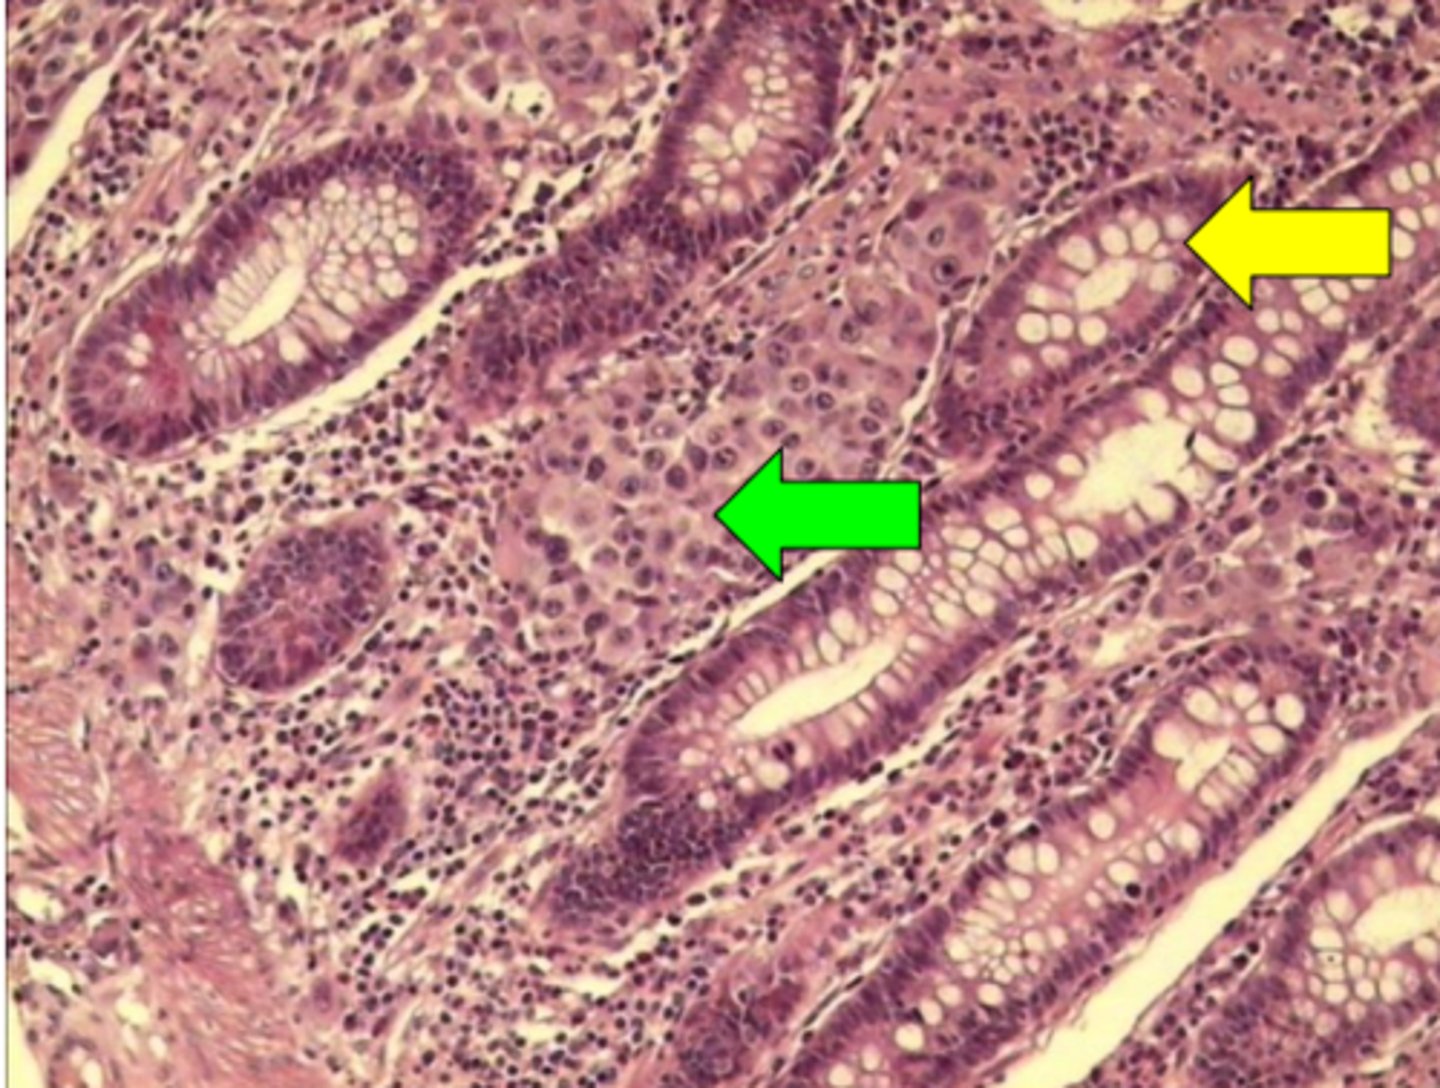

Melanomas metastāze zarnas sieniņā

Melanomas metastāze zarnas sieniņā. Anti - CD34

Melanomas metastāze zarnas sieniņā. Anti - CK AE1 / AE3

Melanomas metastāze zarnas sieniņā. Anti - HMB-45